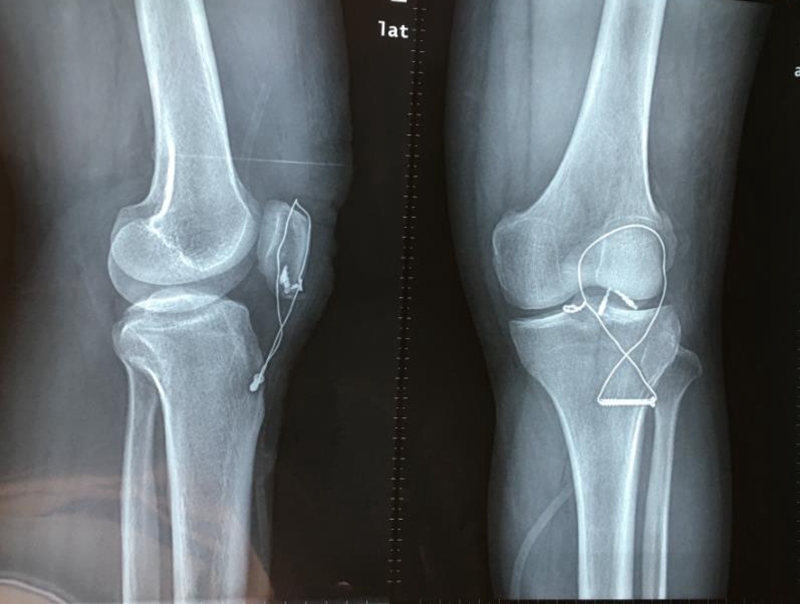

第二步钢丝张立带固定:

胫骨结节处横行置入一枚空心钛钉,18号不锈钢丝(直径1.2mm)穿过空心钛钉,然后向近侧U形或8字形绕过髌骨及股四头肌腱扩张部,在引导器引导下紧贴髌骨上缘穿股四头肌腱,注意要在髌骨内外板之间穿过,伸直膝关节,在髌骨内上角打结。

U形或8字钢丝固定示意图

术后影像学